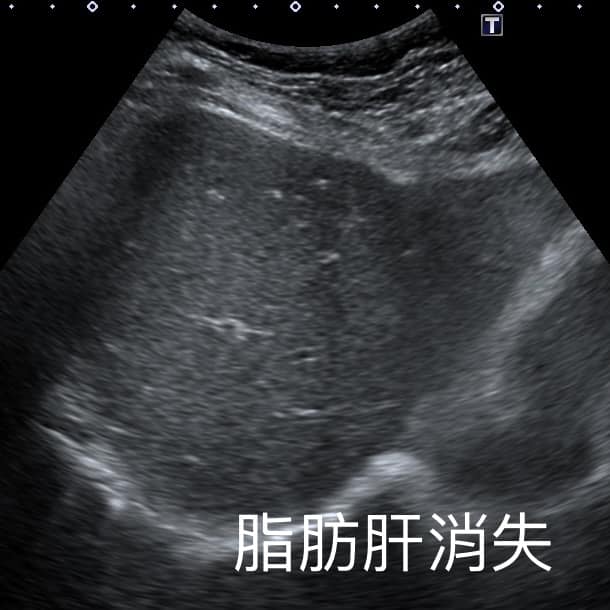

錢政弘醫師在臉書粉絲專頁分享脂肪肝相關案例。60多歲的女病患本來有中度脂肪肝,來照超音波檢查,「肝臟完全正常,脂肪消失了」。一問之下發現阿姨從1年前的66公斤慢慢瘦到51公斤,最近才稍微復胖到56公斤。錢醫師追問阿姨減重成功的祕訣,阿姨表示:「我就少吃水果!」錢醫師一聽倍感驚訝:「少吃水果就可以瘦這麼多!」

肝臟有脂肪在超音波下顏色偏白,翻攝自臉書 (錢政弘 胃腸肝膽科醫師) ,下同。

▲錢醫師說明:脂肪消失後肝臟就恢復深色。